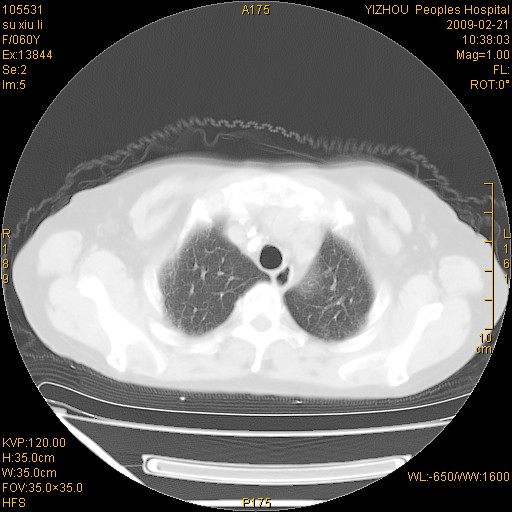

标题: CT18259:两肺间质纤维化? [打印本页]

标题: CT18259:两肺间质纤维化?

女,60岁,反复咳嗽1月。

两肺支扩,以肺为著合并双肺较广范纤维化病变。建议除外结核等病变。

两下肺支扩

符合间质感染,部分纤维化表现

特发性间质纤维化

特发性间质纤维化伴支扩!